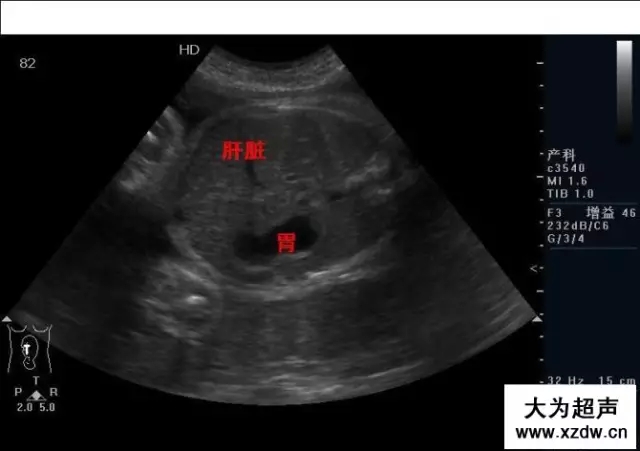

產科超聲正常圖片